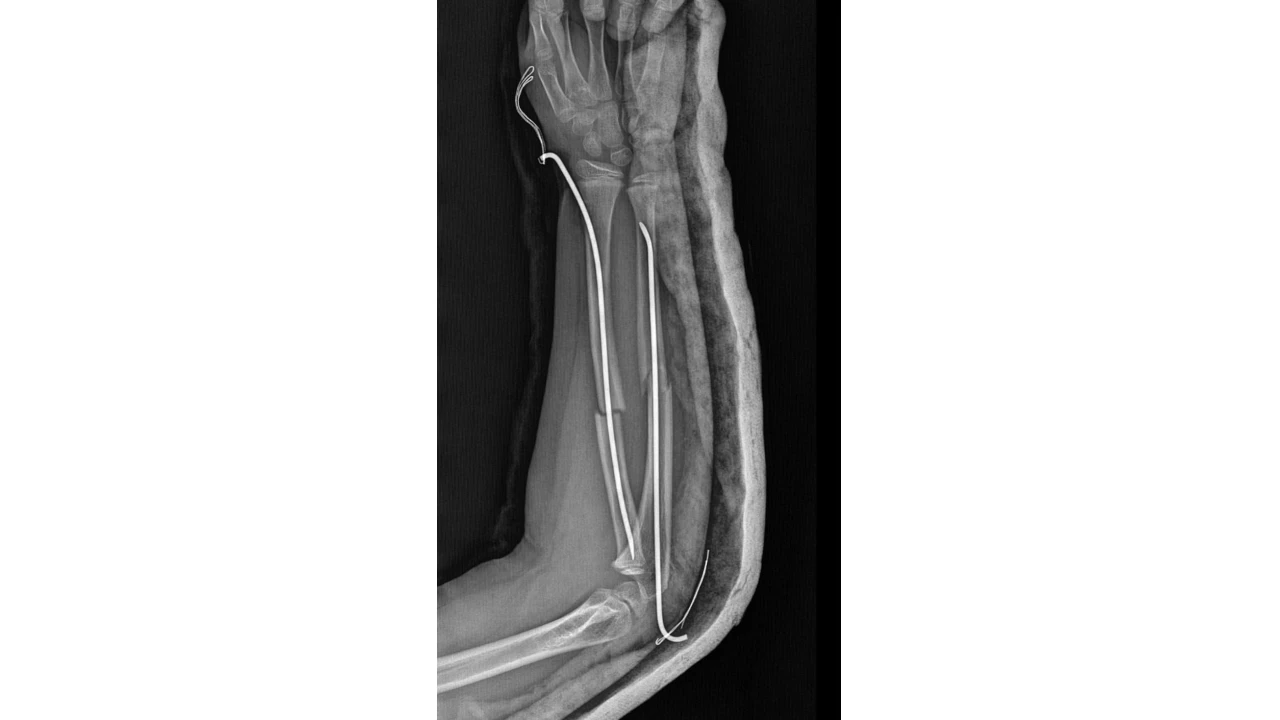

Olay, geçtiğimiz ay Büyükçekmece Tepecik'te bulunan bir ilkokulda meydana geldi. İddiaya göre 8 yaşındaki Y.K.Ş. okulda bir süredir kendisini rahatsız eden 9 yaşındaki çocuk tarafından darp edilerek kolu ikiye katlandı. Y.K.Ş.'nin 2'ye katlanan kolu 2 ayrı yerinden kırıldı. Öğretmenler Y.K.Ş.'nin ailesini arayarak, 'oğlunuz arkadaşıyla kavga etti duvara çarptı' denildi. Oğlunu okuldan alıp hastaneye götüren anne Songül Gökdemir, oğlunun kolunun 2 ayrı yerinden kırıldığını öğrenip ameliyata alınacağını duyduğunda büyük şok yaşadı.

Konuyla ilgili anne Gökdemir savcılığa giderek şikayetçi oldu. Savcılıktan ise 'söz konusu Suça Sürüklenen Çocuğun yaşının 12'den küçük olduğu gerekçesi ile kovuşturmaya yer yoktur' kararı çıktı. Anne Gökdemir karara itiraz ederken mağdur Y.K.Ş. ise haftalardır okula gidemiyor. Eğitimi aksayan çocuğun 2 hafta sonra ise platinlerinin çıkarılması için yeniden ameliyata gireceği öğrenildi.